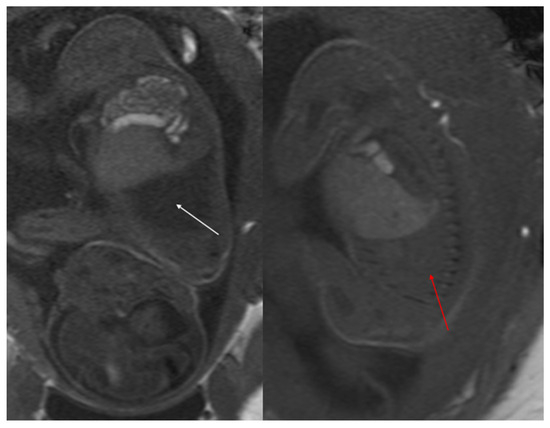

Figure 1. CPAM type I. HASTE oblique sagittal (a) and True FISP (b) MRI scans taken at 28 weeks of gestation reveal a large fluid-filled mass with bright T2 signal in the right chest (arrows). This abnormality results in a shift of the heart toward the left side of the mediastinum.

Figure 2. CPAM type II. Axial HASTE T2 MR images show a hyperintense lesion characterized by at least six cystic images (red arrow) of 2–6 mm at the lung base, with extension to the right posterior lung (orange arrow). No compression on the diaphragm or mediastinum. Minimal pleural effusion layer (white arrow).